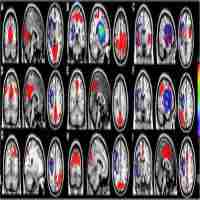

| Abstract | The brain active patterns were organized differently under resting states of eyes open (EO) and eyes closed (EC). The altered voxel-wise and regional-wise resting state active patterns under EO/EC were found by static analysis. More importantly, dynamical spontaneous functional connectivity has been observed in the resting brain. To the best of our knowledge, the dynamical mechanisms of intrinsic connectivity networks (ICNs) under EO/EC remain largely unexplored. The goals of this paper were twofold: 1) investigating the dynamical intra-ICN and inter-ICN temporal patterns during resting state; 2) analyzing the altered dynamical temporal patterns of ICNs under EO/EC. To this end, a cohort of healthy subjects with scan conditions of EO/EC were recruited from 1000 Functional Connectomes Project. Through Hilbert transform, time-varying phase synchronization (PS) was applied to evaluate the inter-ICN synchrony. Meanwhile, time-varying amplitude was analyzed as dynamical intra-ICN temporal patterns. The results found six micro-states of inter-ICN synchrony. The medial visual network (MVN) showed decreased intra-ICN amplitude during EC relative to EO. The sensory-motor network (SMN) and auditory network (AN) exhibited enhanced intra-ICN amplitude during EC relative to EO. Altered inter-ICN PS was found between certain ICNs. Particularly, the SMN and AN exhibited enhanced PS to other ICNs during EC relative to EO. In addition, the intra-ICN amplitude might influence the inter-ICN synchrony. Moreover, default mode network (DMN) might play an important role in information processing during EO/EC. Together, the dynamical temporal patterns within and between ICNs were altered during different scan conditions of EO/EC. Overall, the dynamical intra-ICN and inter-ICN temporal patterns could benefit resting state fMRI-related research, and could be potential biomarkers for human functional connectome. |